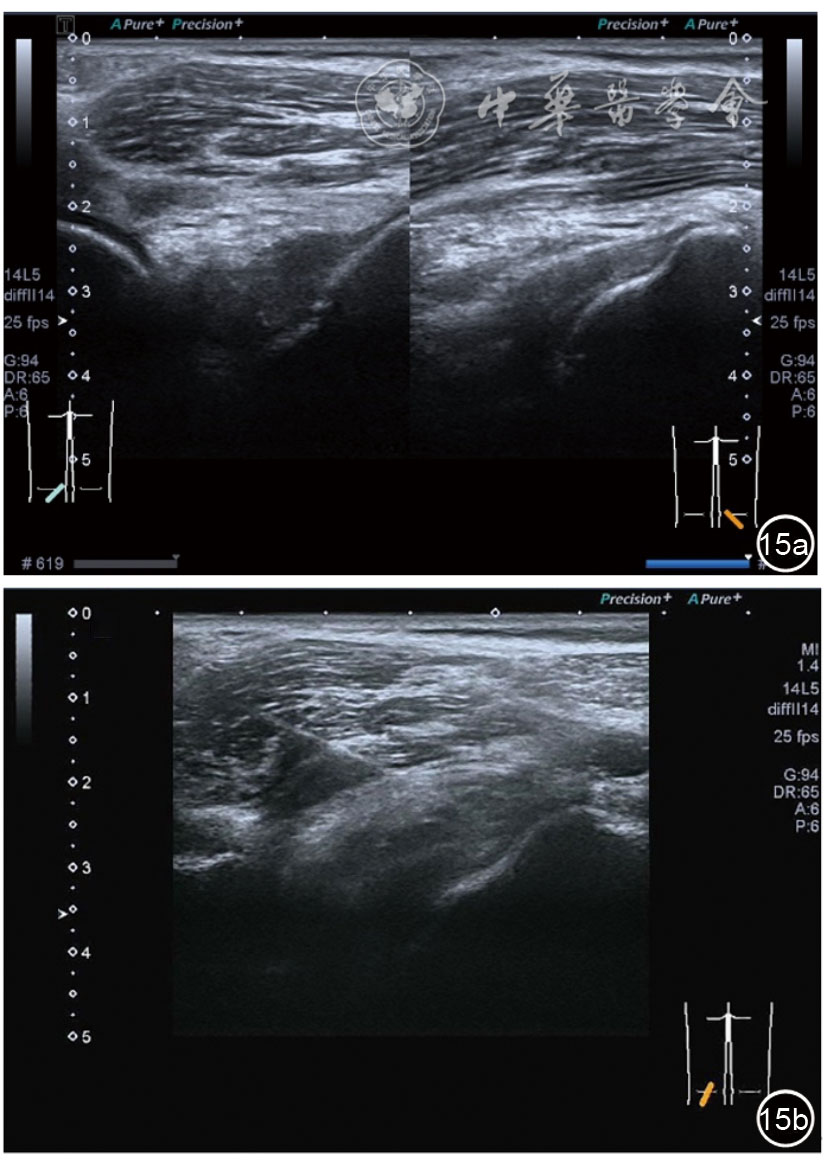

2.膝关节静态结构治疗。动力平衡失调后,继发静态结构变化,出现内外侧副韧带、交叉韧带、脂肪垫、半月板等结构变化。这里介绍半月板与交叉韧带的处理。(1)膝关节静态结构半月板治疗。在膝关节骨关节炎中主要是突出和损伤。突出主要发生于膝内翻引起的内侧半月板突出,引起内侧副韧带的张力增高。内侧半月板与内侧副韧带相连,是引起膝关节内侧疼痛的主要原因之一。治疗主要是针刀剥离松解,部分损伤可行PRP注射。①半月板突出针刀剥离松解治疗。针刀治疗主要是松解和减压,缓解疼痛,不能复位。以内侧半月板突出治疗为例。患者平卧位,髋轻度外展外旋,膝关节屈曲30°,膝下垫一软枕。选用10 MHz超声探头,穿刺区域常规消毒,探头涂抹耦合剂后套入无菌手套碘伏消毒或使用无菌耦合剂。将探头置于患者皮肤表面,内侧关节间隙长轴扫查,找到半月板突出最高点,用25G针头,抽吸1%利多卡因3 ml逐层麻醉直到半月板。选用直径1 mm的Ⅰ型2号针刀从头侧向足侧方向在内侧副韧带与半月板之间,以及半月板内部进行剥离松解3~5刀拔出针刀(图13),局部压迫5分钟,无菌敷料覆盖。②半月板损伤PRP注射治疗。半月板损伤主要表现为髌下痛,伸膝加重,查体在髌下髌韧带与侧副韧带之间,沿关节间隙有固定或局限性压痛,伸膝过程中尤为明显。MRI可示半月板断裂、损伤。如果出现绞索,严重影响功能需手术治疗。半月板损伤治疗,以注射PRP修复为主。以内侧半月板后角损伤为例。患者俯卧位,治疗前准备同半月板突出针刀剥离松解治疗。选用25G注射针头,抽取1%利多卡因2 ml局部麻醉后,制取1.5 ml PRP,穿刺到达半月板撕裂处注射,注射完毕后出针(图14),局部压迫2分钟,无菌敷料覆盖。(2)膝关节静态结构交叉韧带治疗。膝关节骨关节炎交叉韧带损伤多为部分损伤,治疗早期主要为药物或PRP注射,效果不佳时针刀做止点松解。①后交叉韧带损伤药物注射治疗。主要治疗韧带肿胀、无明显断裂患者。患者俯卧位,膝关节伸直位。一般选用10 MHz超声探头,治疗前准备同半月板突出针刀剥离松解治疗。将探头置于患者皮肤表面,后交叉韧带长轴扫查,找到胫骨止点,选用22G长针头,抽吸1%利多卡因3 ml+曲安奈德10 mg,从头侧向足侧方向穿刺到后交叉韧带胫骨止点部位的韧带表面进行注射,注射结束拔出针头(图15),局部压迫2分钟,无菌敷料覆盖。②前交叉韧带损伤PRP注射治疗。患者仰卧位,膝关节伸直。选用10 MHz超声探头,治疗前准备同半月板突出针刀剥离松解治疗。将探头置于患者皮肤表面,短轴扫查,找到前交叉韧带胫骨止点,选用25G针头,抽吸1%利多卡因3 ml逐层麻醉直到韧带止点部位,制备PRP 3 ml注射到前交叉韧带显露部位,注射结束拔出针头(图16),局部压迫2分钟,无菌敷料覆盖。③前交叉韧带损伤针刀剥离松解治疗。体位与治疗前准备同前交叉韧带损伤PRP注射治疗。短轴扫查找到前交叉韧带胫骨止点,选用25G针头,抽吸1%利多卡因3 ml逐层麻醉直到韧带止点部位,选用直径0.6 mm的Ⅰ型2号针刀从外侧向内侧于前交叉韧带胫骨止点部位剥离松解3~5刀拔出针刀(图17),局部压迫5分钟,无菌敷料覆盖。

图15 超声引导下后交叉韧带损伤药物注射治疗